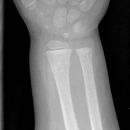

distaler Radiustrümmer Frykman VIII